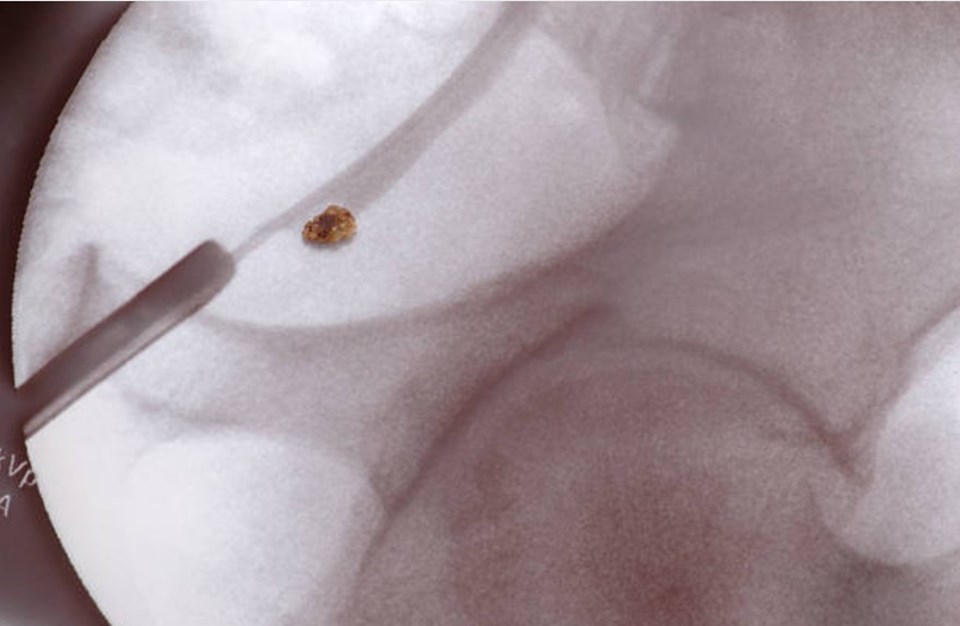

Böbrek kanalları içerisinde genellikle bilinmeyen nedenlere bağlı olarak bazı minerallerin birleşerek oluşturduğu sert yapılara böbrek taşı adı verilir.

Üreteroskopi (Retrograd İntrarenal Cerrahi-RİRC): Böbrek içindeki taşları kıvrılabilir ve ince aletler kullanarak, laser yardımıyla taş kırma yöntemidir. Kıvrılabilir cihazla idrar yolu uç kısmında direkt girilir, üretra, mesane ve üreter geçilerek böbreğe ulaşılır. Taşın boyutu ve bulunduğu bölgeye göre taş bütün olarak çıkartılabilir. Çıkartılamayacak kadar büyük olan taşlar bulunduğu yerde holmium lazer kullanılarak küçük parçalara ayrılarak idrar yoluyla atılması sağlanır.

Böbrek içi lazerle taş kırma işlemi genel anestezi altında gerçekleştirilir. Kırılan taşın kırıntılarının mesaneye akması için genelde böbrekten mesaneye uzanan bir tel(DJ stent) kullanılabilir.

-Böbrek taşının tamamen temizlenip temizlenmediğini belirlenebilmesi için işlem sırasında görüntüleme yöntemleri ile teyit edilir.